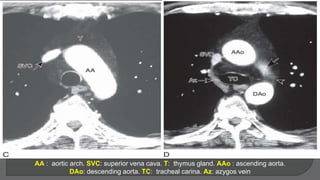

AA : aortic arch. SVC: superior vena cava. T: thymus gland. AAo : ascending aorta.

DAo: descending aorta. TC: tracheal carina. Az: azygos vein

AA : aorticarch. SVC: superior vena cava. T: thymus gland. AAo : ascending aorta. DAo: descending aorta. TC: tracheal carina. Az: azygos vein